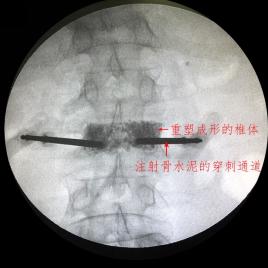

2、经皮穿刺椎体成形术PVP缓解腰部疼痛

可治疗由于骨质疏松引起的椎体压缩性骨折,从而缓解和治疗其引起的腰痛。

通过特殊的穿刺针在X线监护下经皮肤穿刺进入椎体,建立工作通道,将骨水泥或人工骨注入椎体内强化椎体以防止进一步塌陷,治疗和缓解由于椎体骨折和不稳定引起的长期腰痛。